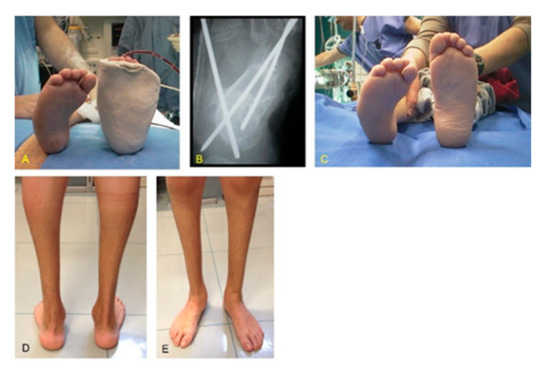

Figure 1. MS (Moebius syndrome) patient with bilateral stiff CF (clubfoot) at 3.5 years of age at the time of relapse surgery. ATL (Achilles tendon lengthening), PR (posterior release), and MR (medial release) were performed at 5 months of age. (A) Adduction deformity left; (B) X-ray in antero-posterior projection showing pathological talus calcaneal angle; (C) plantar view of both feet showing cavus and adduction deformities; (D) clinical aspect in frontal plane showing all components of CF; (E) medial aspect with skin scars after ATL, PR, and MR; (F) X-ray in lateral projection showing pathological talus calcaneal angle.